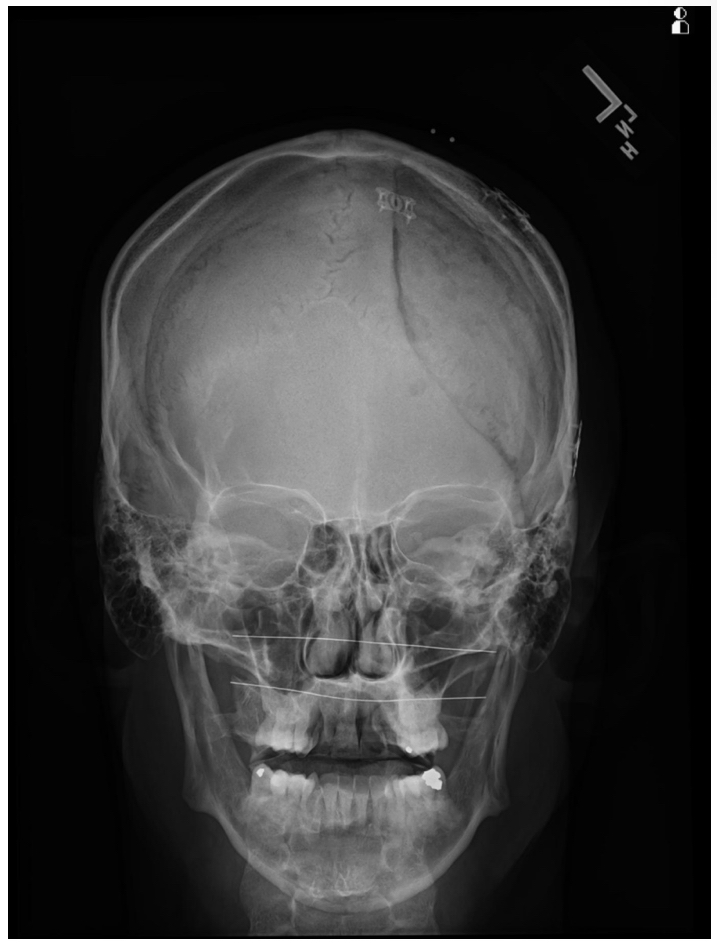

PA Skull

The patient is in the ___ position (or standing facing the bucky).

Instruct the patient to rest ___ and ___ on the table and adjust the head so that the ___and ___ ___ are ___ to the plane of the IR.

Direct the CR ___ to exit the ___ (bridge of nose).

The ___ ___ should fill the orbits. The distance from the lateral border of the ___ to the lateral border of the ___ should be equal on both sides.

The patient is in the prone position (or standing facing the bucky).

Instruct the patient to rest nose and forehead on the table and adjust the head so that the OML and midsagittal plane are perpendicular to the plane of the IR.

Direct the CR perpendicular to exit the Nasion (bridge of nose).

The petrous ridges should fill the orbits. The distance from the lateral border of the skull to the lateral border of the orbit should be equal on both sides.